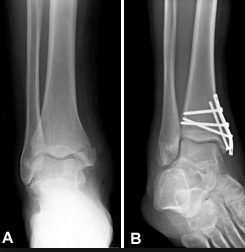

Ankle

Ankle fractures include fractures of the medial, lateral, and/or posterior malleoli.

Medial malleolus fractures are generally the result of an eversion injury whereas lateral malleolus fractures are the result of an inversion injury.

These fractures commonly occur in athletes and as a result of trauma.

Non displaced ankle fractures are treated with a cast, but displaced or unstable fractures require open reduction internal fixation.